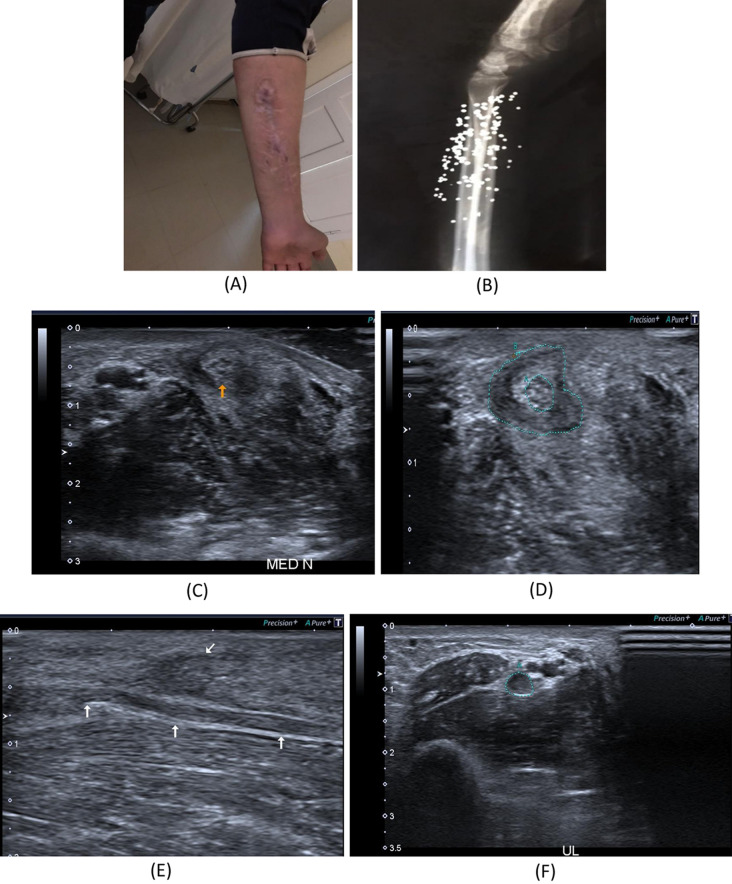

Fig. 4.

A 28-year- old male patient presenting with history gunshot injury to the left forearm since June 2021. He underwent flexor muscles and tendons in addition to median nerve repair. A Patient’s forearm showing scar tissue. B X-ray image of the left forearm multiple retained bullets. C, D B-mode image, transverse axis, shows thickened median nerve(arrow) at proximal forearm with circumferential hypoechoic lesion. E B-mode image, longitudinal axis, shows intact epineurum of the median nerve(arrows) at proximal forearm with superficially related hypoechoic lesion (oblique arrow). F B-mode image, transverse axis, shows thickened hypoechoic ulnar nerve at proximal forearm. G B-mode image, longitudinal axis, shows thick hypoechoic swelling of the left ulnar nerve with loss of fascicular architecture. H B-mode image, transverse axis, abnormal architecture of the left FPL muscle with increased echogenicity and reduced girth as compared to the normal right side. I B-mode image, transverse axis, abnormal architecture of the left FDS muscle with increased echogenicity and reduced girth as compared to the normal right side